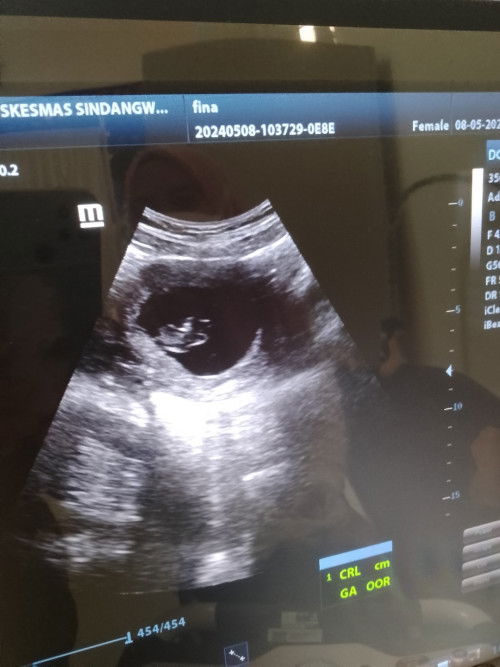

Bun mau tanya, aku USG usia 10 minggu kaya gini yah? Kok kaya belum kelihatan ya bun? Mohon dijawab.

USG 10 week

izin jwb ya bund, mungkin mksd bundanya pngn keliatan lbh jls bentuk janinnya ya? klo mau kaya gtu lebih baik usg nya yng transvaginal bund itu keliatan jelas bngt bentuk janinnya, klo usg 2D mah emng blm keliatan jls bntknya apalgi usia kehamilan yng msih muda gtu bund

klo usia 10w udh keliatan janin segitu udh alhamdulilah bund, klo bunda mau lebih jelas lihat debay nya bisa usg 3D/4D ya bund. sehat selalu bunda dan debay nyaa

tapi udh ada djj'nya bund? soalnya kalo aku kmaren 8w gitu emang masih kecil bgt tapi pas di cek udh ada djj'nya

alhamdulillah sudah bunda

Lah itu udh ada janinnya. Mau kelihatan apa lagi? Emang dokternya juga ga jelasin?

itu udah kelihatan janinnya Bun.